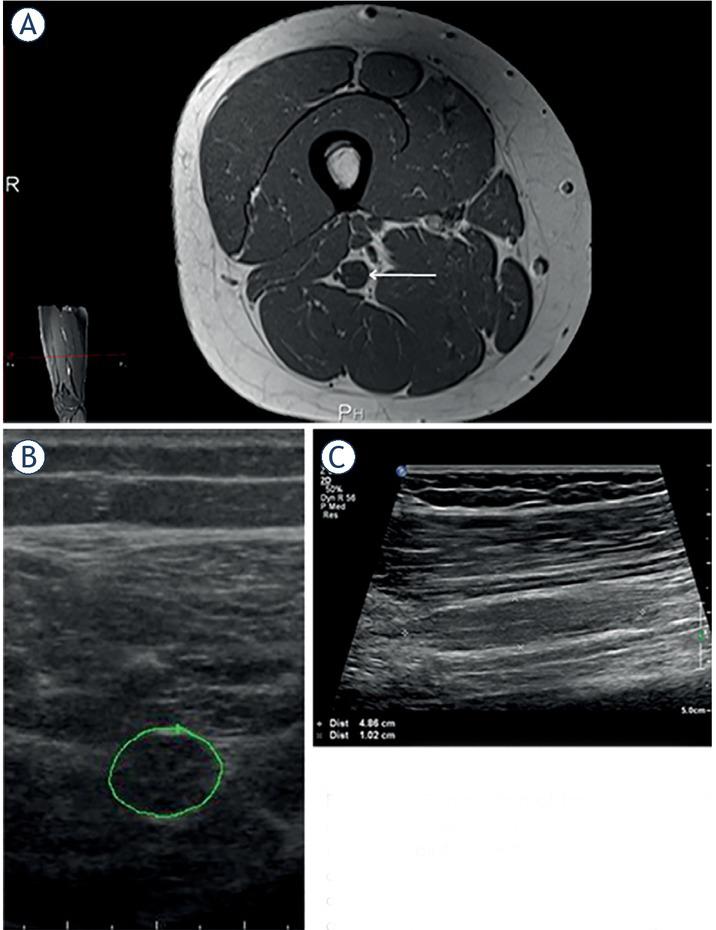

Morphological features of peripheral nerve tumors (PNTs) found on ultrasonographic (US) examination5 of individual patients

| # | Ratio | Shape | Contour | Encapsulation | Echo texture | Nerve position | Nerve transition | Number | Tumor diagnosis |

|---|---|---|---|---|---|---|---|---|---|

| 1 | 5 | Fusiform | Lobulated | Partial | Heterogeneous | Central | Infiltrative | Single | Neurofibroma |

| 2 | ? | Lobulated | Partial | Heterogeneous | ? | ? | Several | Schwannoma* | |

| 3 | 6 | Fusiform | Smooth | Whole | Heterogeneous | Central | Poorly defined | Single | Schwannoma |

| 4 | 6 | Fusiform | Fusiform | None | Heterogeneous | Central | Infiltrative | Several | Neurofibroma |

| 5 | 8 | Fusiform | Lobulated | Partial | Heterogeneous | Central | Infiltrative | Single | Perineurioma |

| 6 | > 10 | Fusiform | Lobulated | Partial | Heterogeneous | ? | ? | Single | Perineurioma |

| 7 | 6 | Fusiform | Smooth | None | Homogenous | Central | Infiltrative | Single | Perineurioma |

| 8 | 3 | Oval | Smooth | Whole | Heterogeneous | Central | Poorly defined | Single | Schwannoma* |

| 9 | > 10 | Fusiform | Lobulated | Partial | Heterogeneous | Eccentric | Infiltrative | Single | Neurofibroma |

| 10 | 5 | Fusiform | Smooth | Whole | Heterogeneous | Central | Infiltrative | Several | Perineurioma |

| 11 | 1,5 | Oval | Smooth | Whole | Homogenous | Eccentric | ? | Single | Schwannoma* |

| 12 | 2,5 | Oval | Smooth | Whole | Heterogeneous | Central | Poorly defined | Single | Schwannoma* |

| 13 | 2,5 | Oval | Smooth | Whole | Heterogeneous | Central | Poorly defined | Several | Neurofibroma |

| 14 | 4 | Fusiform | Lobulated | Partial | Heterogeneous | Central | Infiltrative | Several | Neurofibroma* |

| 15 | 1,7 | Oval | Smooth | Whole | Heterogeneous | Eccentric | Poorly defined | Single | Schwannoma |

Demographic, anatomical, clinical, electrodiagnostic (EDx) and ultrasonographic (US) features of patients with peripheral nerve tumors (PNTs)

| # | Gender | Age | Side | Nerve | Location | Symptoms & Signs | CMAP amp. (mV) | SNAP amp. (μ V) | Tumor CSA (mm2) | Tumor diagnosis | Other |

|---|---|---|---|---|---|---|---|---|---|---|---|

| 1 | Male | 69 | R | Ulnar | Elbow | AWS | 43 | Neurofibroma | |||

| 2 | Male | 24 | L | #Radial | Upper arm | W | 0.2 | 4 | 24 | Schwannoma* | NF2 |

| 3 | Male | 66 | R | Median | Forearm | Æ | 6.9 | 5 | 49 | Schwannoma | |

| 4 | Male | 16 | L | #Median | Upper arm | WS | 61 | Neurofibroma | NF1 | ||

| 5 | Female | 26 | R | Ulnar | Forearm | AWS | 0.2 | 0 | 30 | Perineurioma | |

| 6 | Female | 18 | L | Sciatic | Thigh | AWS | 0.4 | 0 | 109 | Perineurioma | |

| 7 | Female | 18 | R | Fibular | Knee | AWS | 0 | 0 | 47 | Perineurioma | |

| 8 | Male | 47 | L | Ulnar | Elbow | M | 7.6 | 3 | 348 | Schwannoma* | |

| 9 | Female | 58 | R | Median | Forearm | P | 7.6 | 16 | 45 | Neurofibroma | |

| 10 | Female | 22 | R | Sciatic | Thigh | AWS | 0 | 0 | 97 | Perineurioma | |

| 11 | Female | 34 | R | Tibial | Ankle | PAWS | 10.6 | 7 | 1250 | Schwannoma* | |

| 12 | Male | 63 | L | Ulnar | Elbow | L | 8.2 | 5 | 368 | Schwannoma* | |

| 13 | Female | 52 | R | #Ulnar | Forearm | 6.2 | 12 | 212 | Neurofibroma | NF? | |

| 14 | Male | 24 | R | #Median | Upper arm | P | 6.3 | 33 | 26 | Neurofibroma* | NF1 |

| 15 | Female | 33 | L | Tibial | Ankle | L | 92 | Schwannoma |